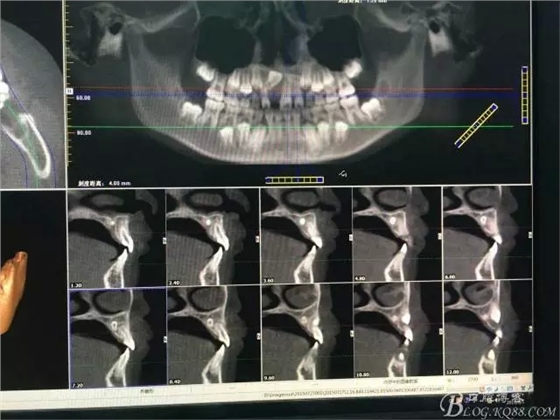

圖1.術(shù)前CBCT檢查:11牙冠90°唇側(cè)傾斜,21和22根尖區(qū)腭側(cè)有一埋伏多生牙

圖2.術(shù)前的CBCT的三維影像重建:多生牙的位置

圖3.右上11的三維影像位置。